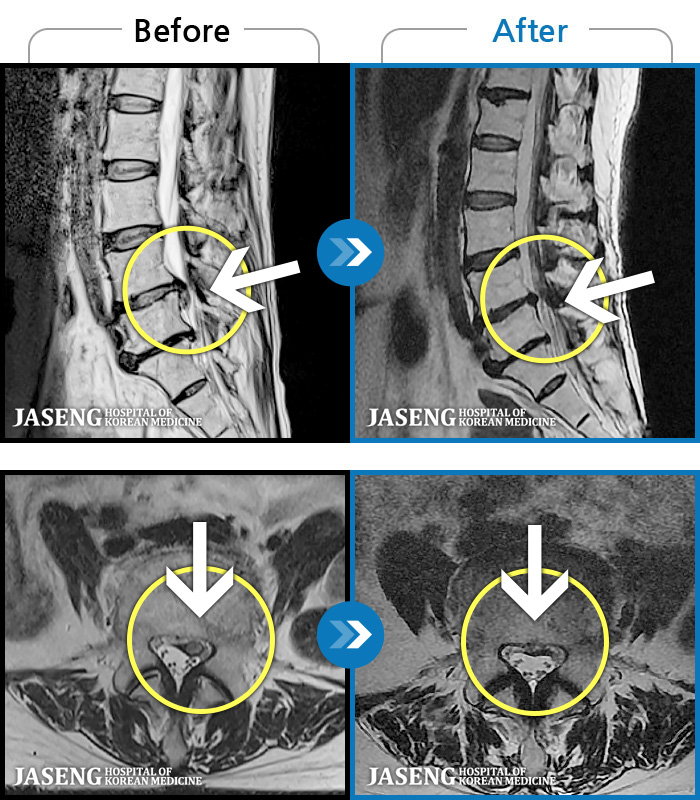

1,291 MRI ũ ʸ Ȯϼ.

[] 03.04.01~09.11.01